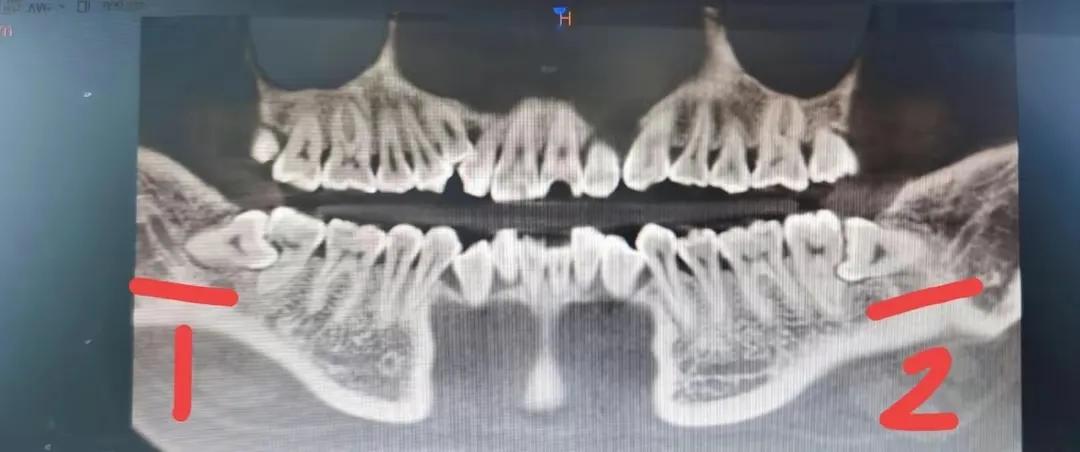

五月份那次拔的“1”,没有留下洞

但这一次拔牙,医生采用的方法是智齿有多大,伤口就有多大,并不会去用刀片划开其他的地方,所以第二次拔牙脸没有肿,当天晚上就能吃饭了,刚开始我还很庆幸,觉得选对了医生,一周后才发现更大的麻烦来了。那颗智齿拔开后,就剩下一个洞,吃任何东西都会落进那个洞里面,我实在是不放心,因为没有经历过,所以我决定去找医生看看。